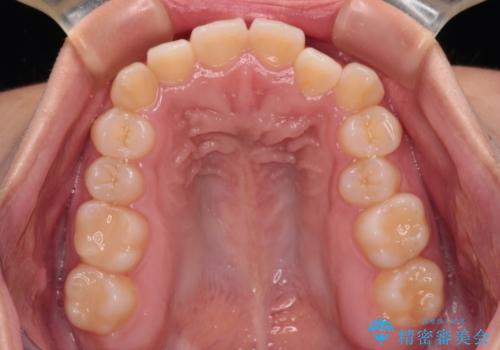

- 上下前歯のクロスバイトと叢生を気にして来院された患者様です。

インビザラインでの治療を希望されていて、デコボコの程度が中等度であり、安価なパッケージにて対応可能と判断されたため、インビザライン・モデレートを用いて矯正治療を行うこととしました。